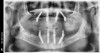

Figure 15: A pre-operative panoramic radiograph reveals several issues.

Figure 15

This workflow is also completed in two patient appointments. The same records and esthetic evaluation that was done in the dynamic navigation workflow are also completed for the static guide process (Figure 14 and Figure 15). A digital denture design is made (Figure 16), and once approved, the patented occlusal locks are added. No positioning handle is needed for this specific conversion denture/static guide (SurgiDenture; Global Dental Science, LLC), as the denture will be anchored to the patient with stabilizing pins. The virtual implant planning is made in relation to the digital denture design (Figure 17). The implant coordinates are exported from the planning program in relation to the denture design so that specific guidance holes can be programmed and ultimately milled into the denture (Figure 18 and Figure 19). These holes are compatible with a guided surgery drilling system (NobelGuide; Nobel Biocare).7,8